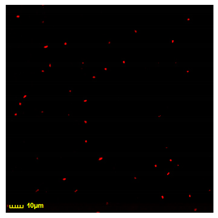

3.7.1. Comparison of the Phagocytosis for BALF Macrophages in Comparison with Model CD206+ Macrophages’ Cell Lines

3.7.2. Phagocytic Activity of CD206+ Macrophages from BALF Towards Different Strains of E. coli Cells